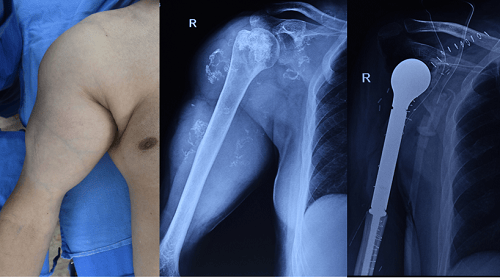

Bone cancer surgery involves the removal of cancerous bone tumors and surrounding tissues to treat bone cancer. This procedure aims to eliminate the tumor while preserving as much healthy bone and surrounding tissue as possible. It is often combined with other treatments like chemotherapy or radiation to enhance effectiveness and prevent recurrence.

An incision is made to remove the cancerous bone and surrounding healthy tissue.

Step-3: Reconstruction

Reconstruction may involve grafts or prosthetics to restore function and appearance after tumor removal.